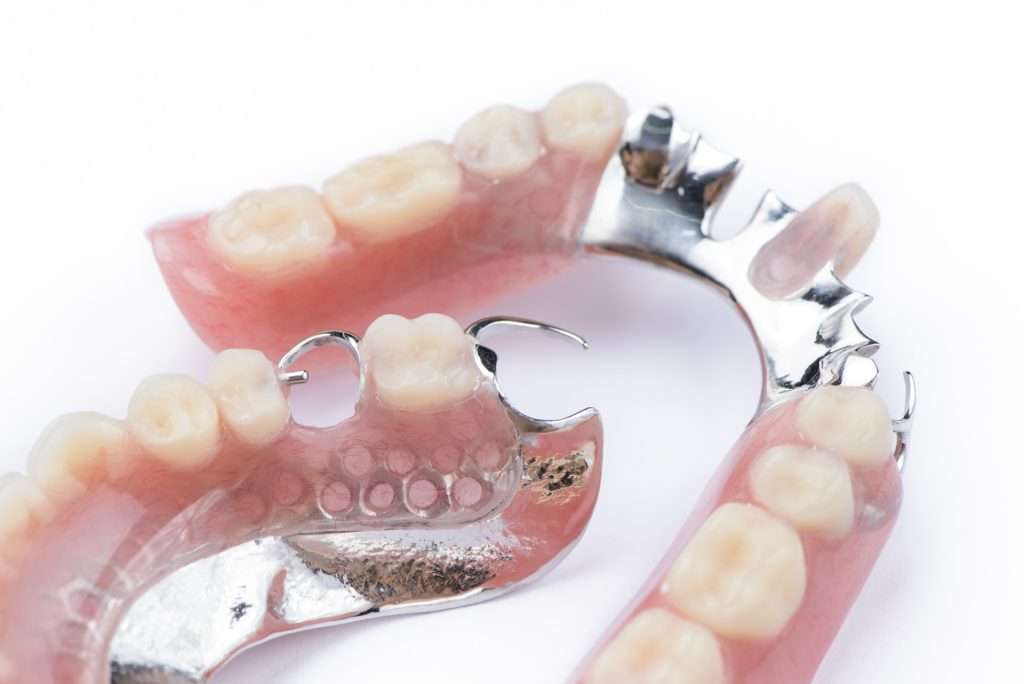

Your Complete FAQ Guide to Bone Grafting and Jawbone Health

Your Complete FAQ Guide to Bone Grafting and Jawbone Health A healthy jawbone is the hidden foundation of a functional, aesthetically pleasing smile. While teeth are the visible components of the oral cavity, they rely entirely on the density and volume of the underlying bone for support. When that foundation is compromised, it can lead […]